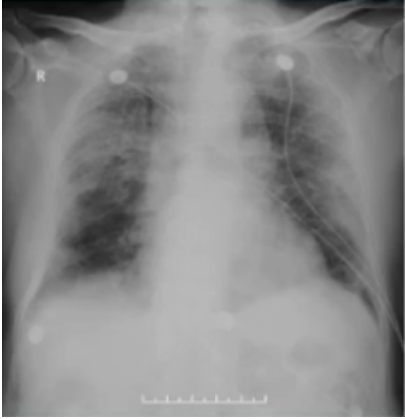

入院前胸部CT(2022-12-27):双肺弥漫性间质性改变,胸膜下为主,提示肺气肿合并间质性改变,考虑慢阻肺合并病毒性肺炎(图1)

图1  患者入院前胸部CT(2022-12-27)